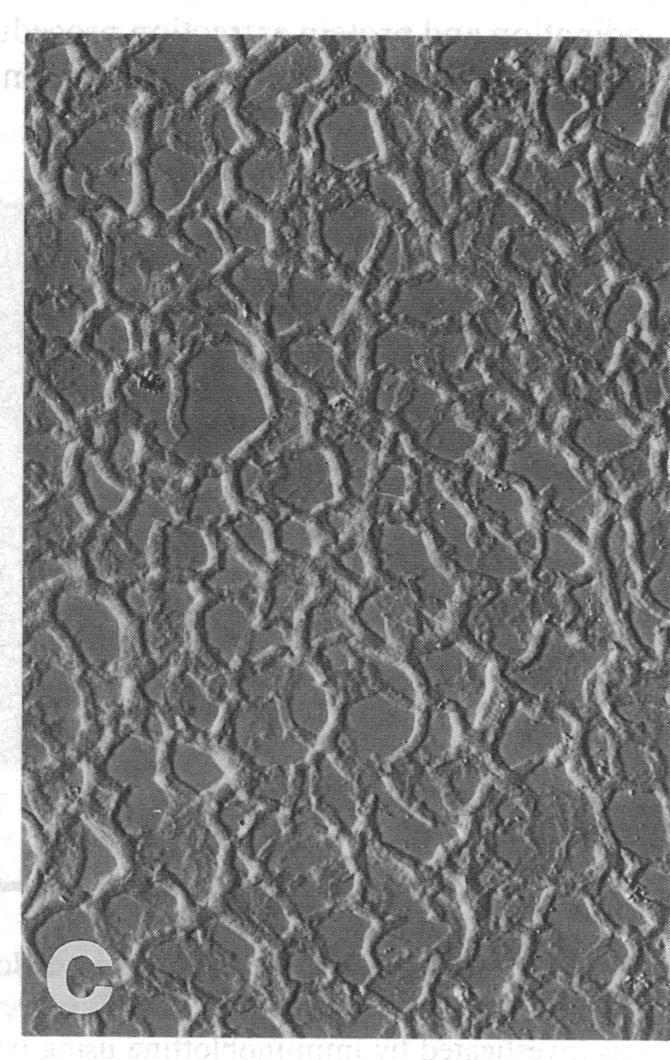

Microvascular endothelial cells in vivo exhibit a plastic phenotype, forming a nonproliferative, differentiated capillary network, while retaining their ability to respond to injury by proliferation, migration and neovascularization. The presence of PDGF receptors and PDGF responsiveness in microvascular endothelial cells and the significance of PDGF isoforms in the control of endothelial cell growth and differentiation remain controversial. Since culture of microvascular endothelial cells in a three-dimensional (3D) system induced cell differentiation and angiogenesis and inhibited proliferation, the present study investigates the role of different extracellular matrix environments in inducing different microvascular endothelial cell phenotypes on microvascular endothelial cell PDGF receptor expression and PDGF responsiveness. In conventional two-dimensional (2D) culture, microvascular endothelial cells expressed both PDGF receptor alpha and beta chains. Suramin treatment demonstrated continuous downregulation of the alpha receptor surface expression. PDGF BB and, to a lesser extent, PDGF AB were mitogenic in 2D-culture, PDGF AA failed to induce any proliferative response despite inducing receptor autophosphorylation. During in vitro angiogenesis induced by 3D-culture, both PDGF receptors were rapidly downregulated. Assessment of cell proliferation showed quiescent cells and PDGF unresponsiveness. We conclude that the induction of a differentiated phenotype during in vitro angiogenesis (tube formation) driven in part by the spatial organization of the surrounding matrix is associated with a downregulation of PDGF receptors. Identification of the molecular cell-matrix interactions involved in this receptor regulation may allow for targeted manipulation of cell growth in vivo and lead to novel therapeutic applications for PDGF.